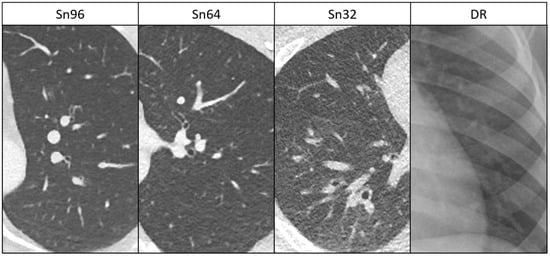

3.2. Anatomical Structures